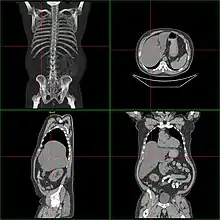

| Computerized tomography of affected person with hepatomegaly | |

Computerized tomography (CT) can give accurate anatomical information for a complete diagnosis.[22]